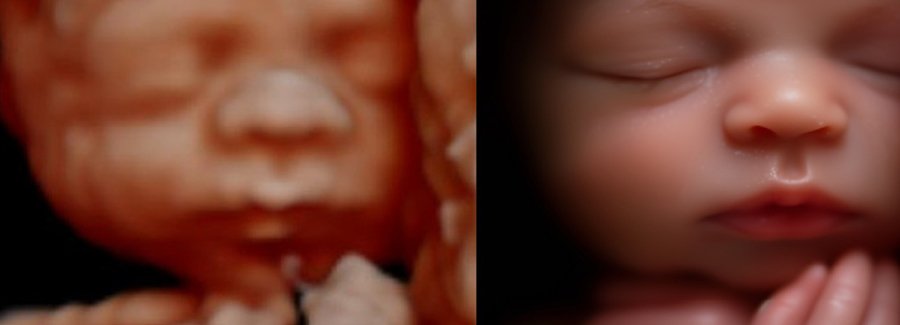

Often referred to as 5D, HD or FRV (fetal realistic view), 5D/HD is the newest development in pregnancy imaging. It captures and combines high definition volume data to create automated images with amazing color and clarity so you can see your baby as though you were looking from inside the womb.